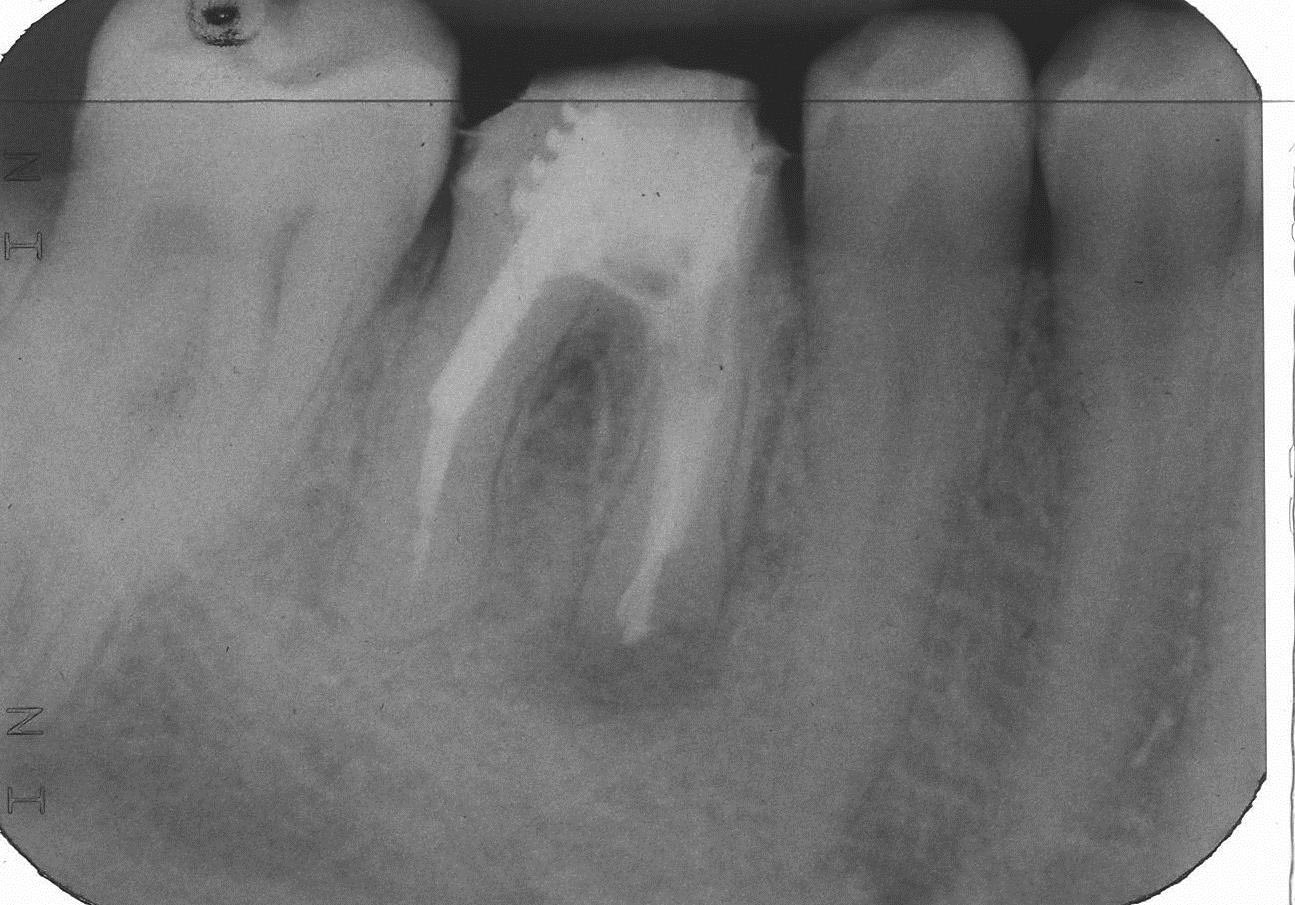

FL-4 Veröffentlicht 6. Oktober 2013 am 1295 × 905 in Teilrevision Zahn 46 – Wie würden Sie entscheiden?